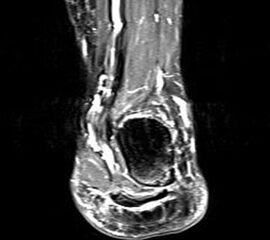

Hier befindet sich ca. 3-5 cm proximal des Tuber calcanei ein als „kritische Zone“ benannter Bezirk, der durch eine ungünstige arterielle Blutzufuhr gekennzeichnet ist (letzte Wiese). Hier finden sich häufig spindelförmige Schwellungen, die bei MRT-Diagnostik nicht selten partielle Nekrosen und Partialrupturen der Achillessehne aufweisen (Abb. 14).

Unabhängig davon können insbesondere chronische Insertionstendinosen der Achillessehne von Partialrupturen (Abb. 15) und erosiven Läsionen des dorsalen Fersenbeines begleitet sein.

Bildgebung

Die sonographische Diagnostik eignet sich primär zur Erkennung schmerzhafter Prozesse im Verlauf der Achillessehne und kann bei Bedarf durch Röntgen bzw. MRT ergänzt werden. Besonders bei längeren Verläufen und kräftigen spindelförmigen Schwellungen (>9mm, Normwert <5mm) im Bereich der kritischen Zone sollte ein MRT zum Ausschluss von Nekrosezonen und Partialrupturen vor Therapiebeginn veranlasst werden. Die sonographisch leicht zu erfassende Veränderung der Sehnendicke im mittleren Sehnenanteil ist ein guter Indikator für die Schwere der Erkrankung und die Beurteilung des Behandlungsverlaufes. Die sichtbaren Veränderungen am distalen knöchernen Ansatz der Sehne sind diskreter.

Insbesondere bei größeren Partialrupturen (Abb. 14) sollten operative Verfahren erörtert werden. Kleinere Partialrupturen sind der ESWT gut zugänglich, wie die beiden nachfolgenden Beispiele zeigen: